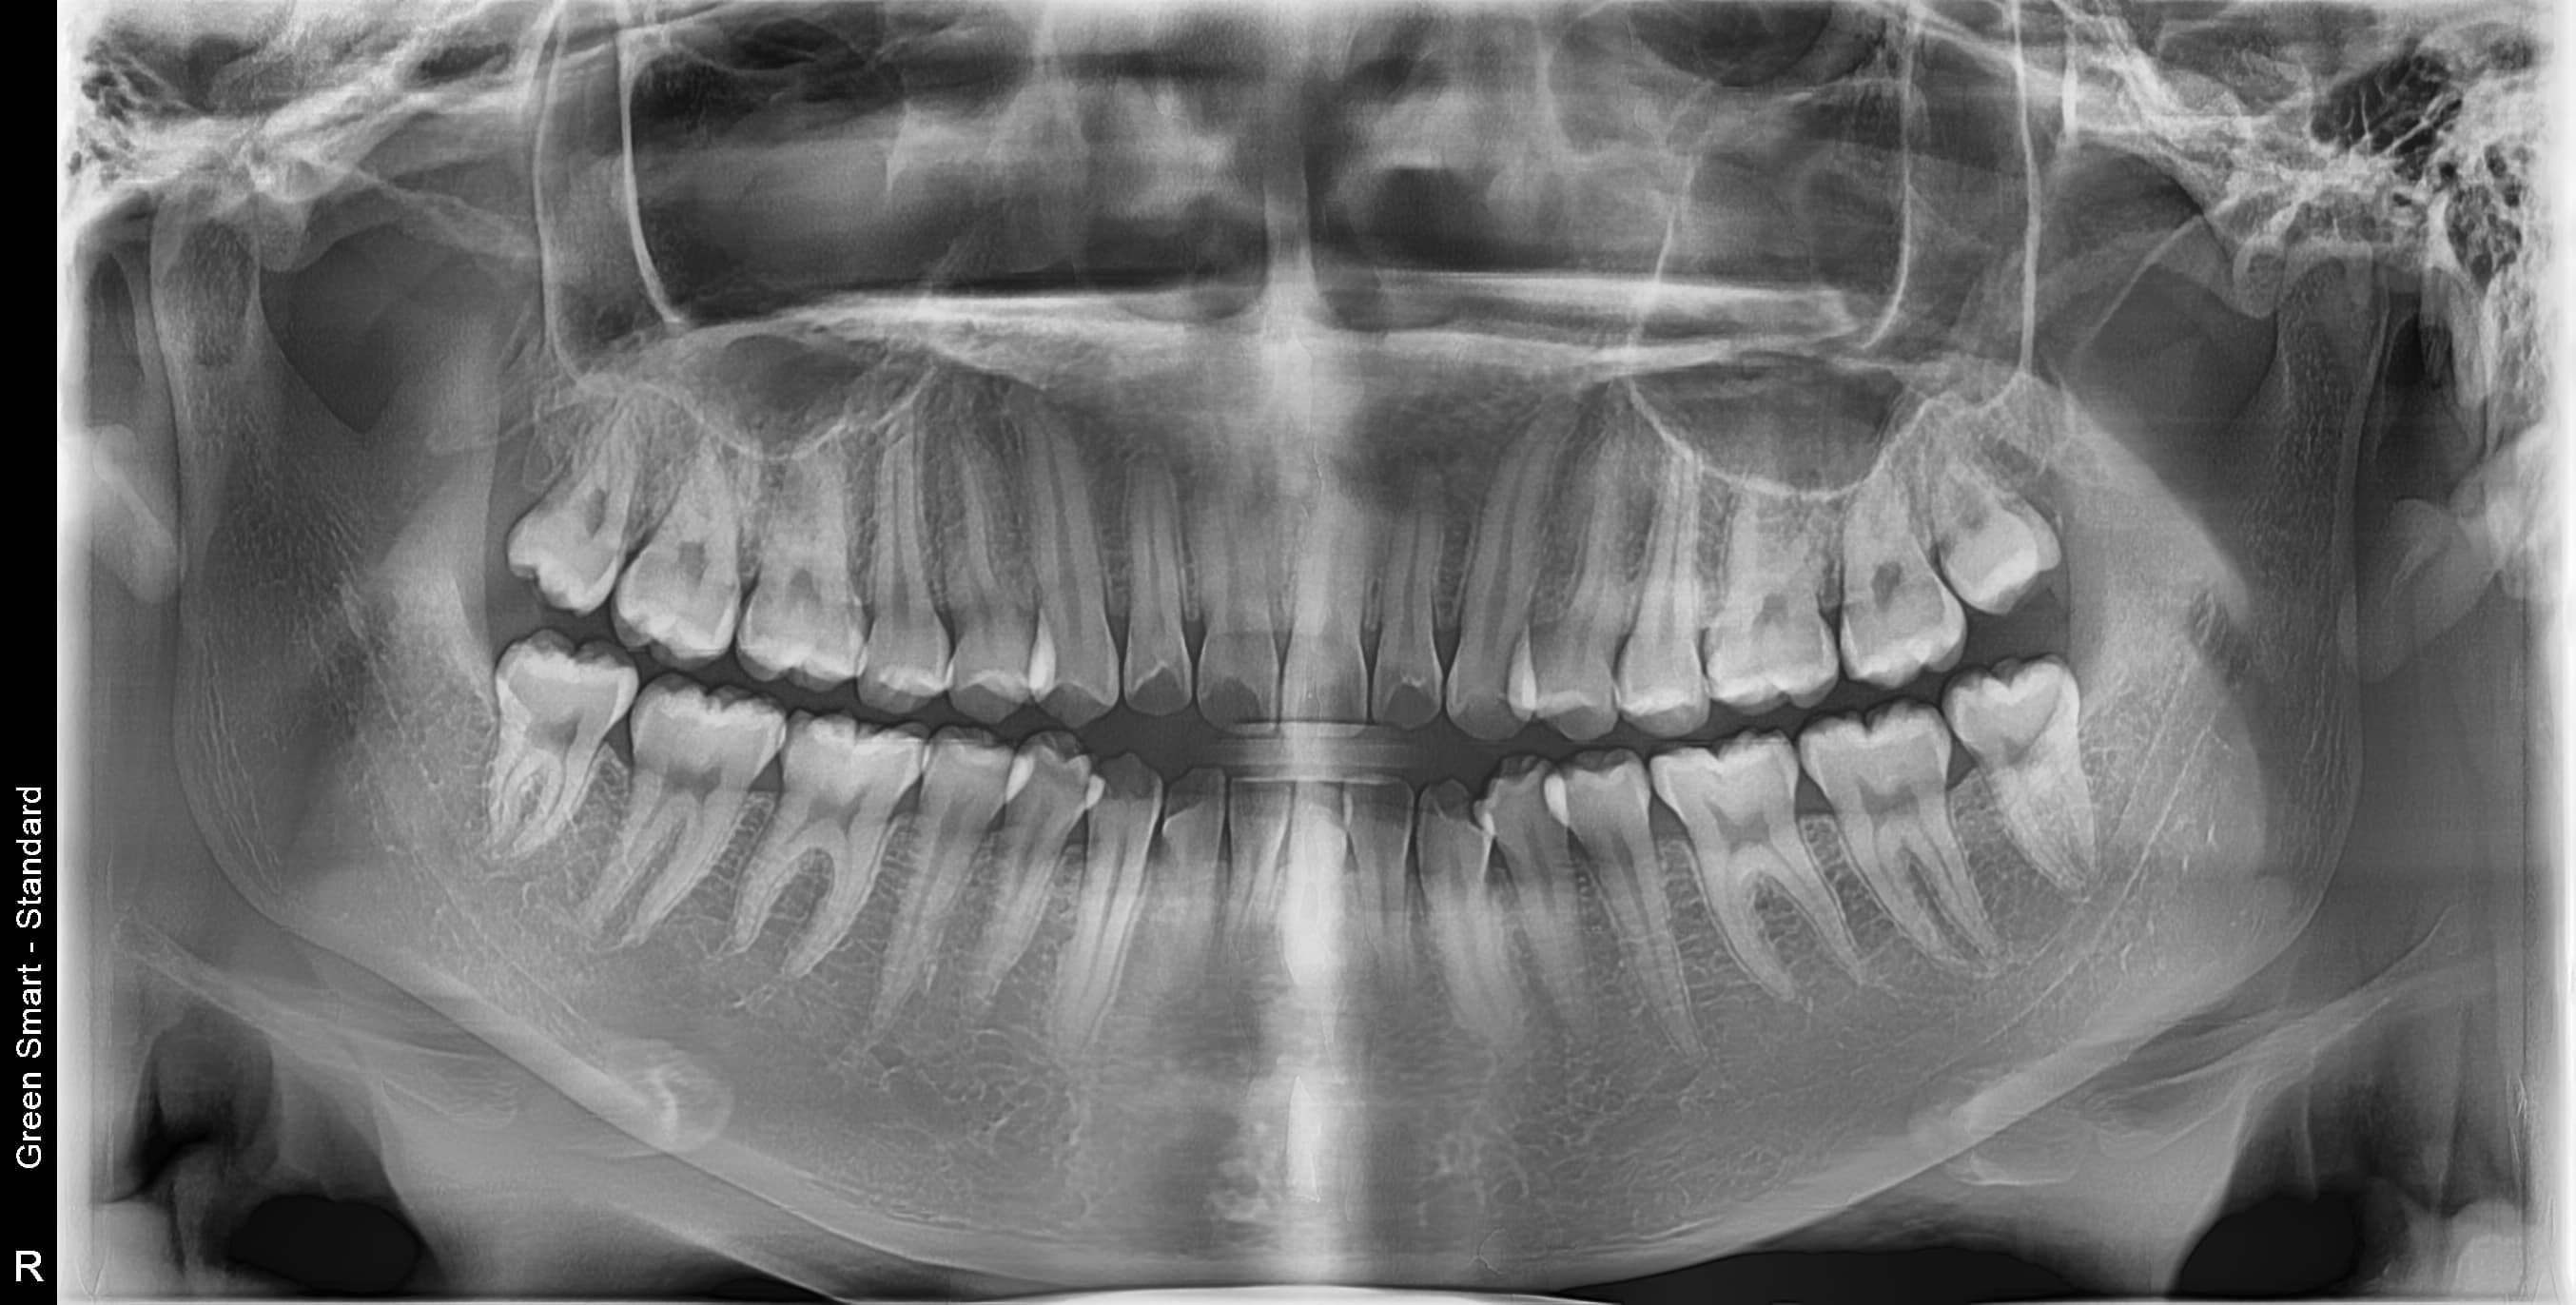

누운 사랑니

옆으로 누워 자라며 옆 치아를 압박할 수 있습니다

저위험

정상 사랑니

정상적으로 자란 사랑니도 관리가 어려워 충치 위험이 높습니다

중위험

부분매복 사랑니

음식물이 끼기 쉽고 염증이 자주 발생합니다

고위험

완전매복 사랑니

낭종 형성 가능성이 있어 조기 발치가 필요합니다

치근만곡 사랑니

뿌리가 구부러져 있어 발치 난이도가 높습니다

즉시 처치 필요

수평매복 사랑니

앞 치아를 밀어 치열 불균형과 충치를 유발합니다